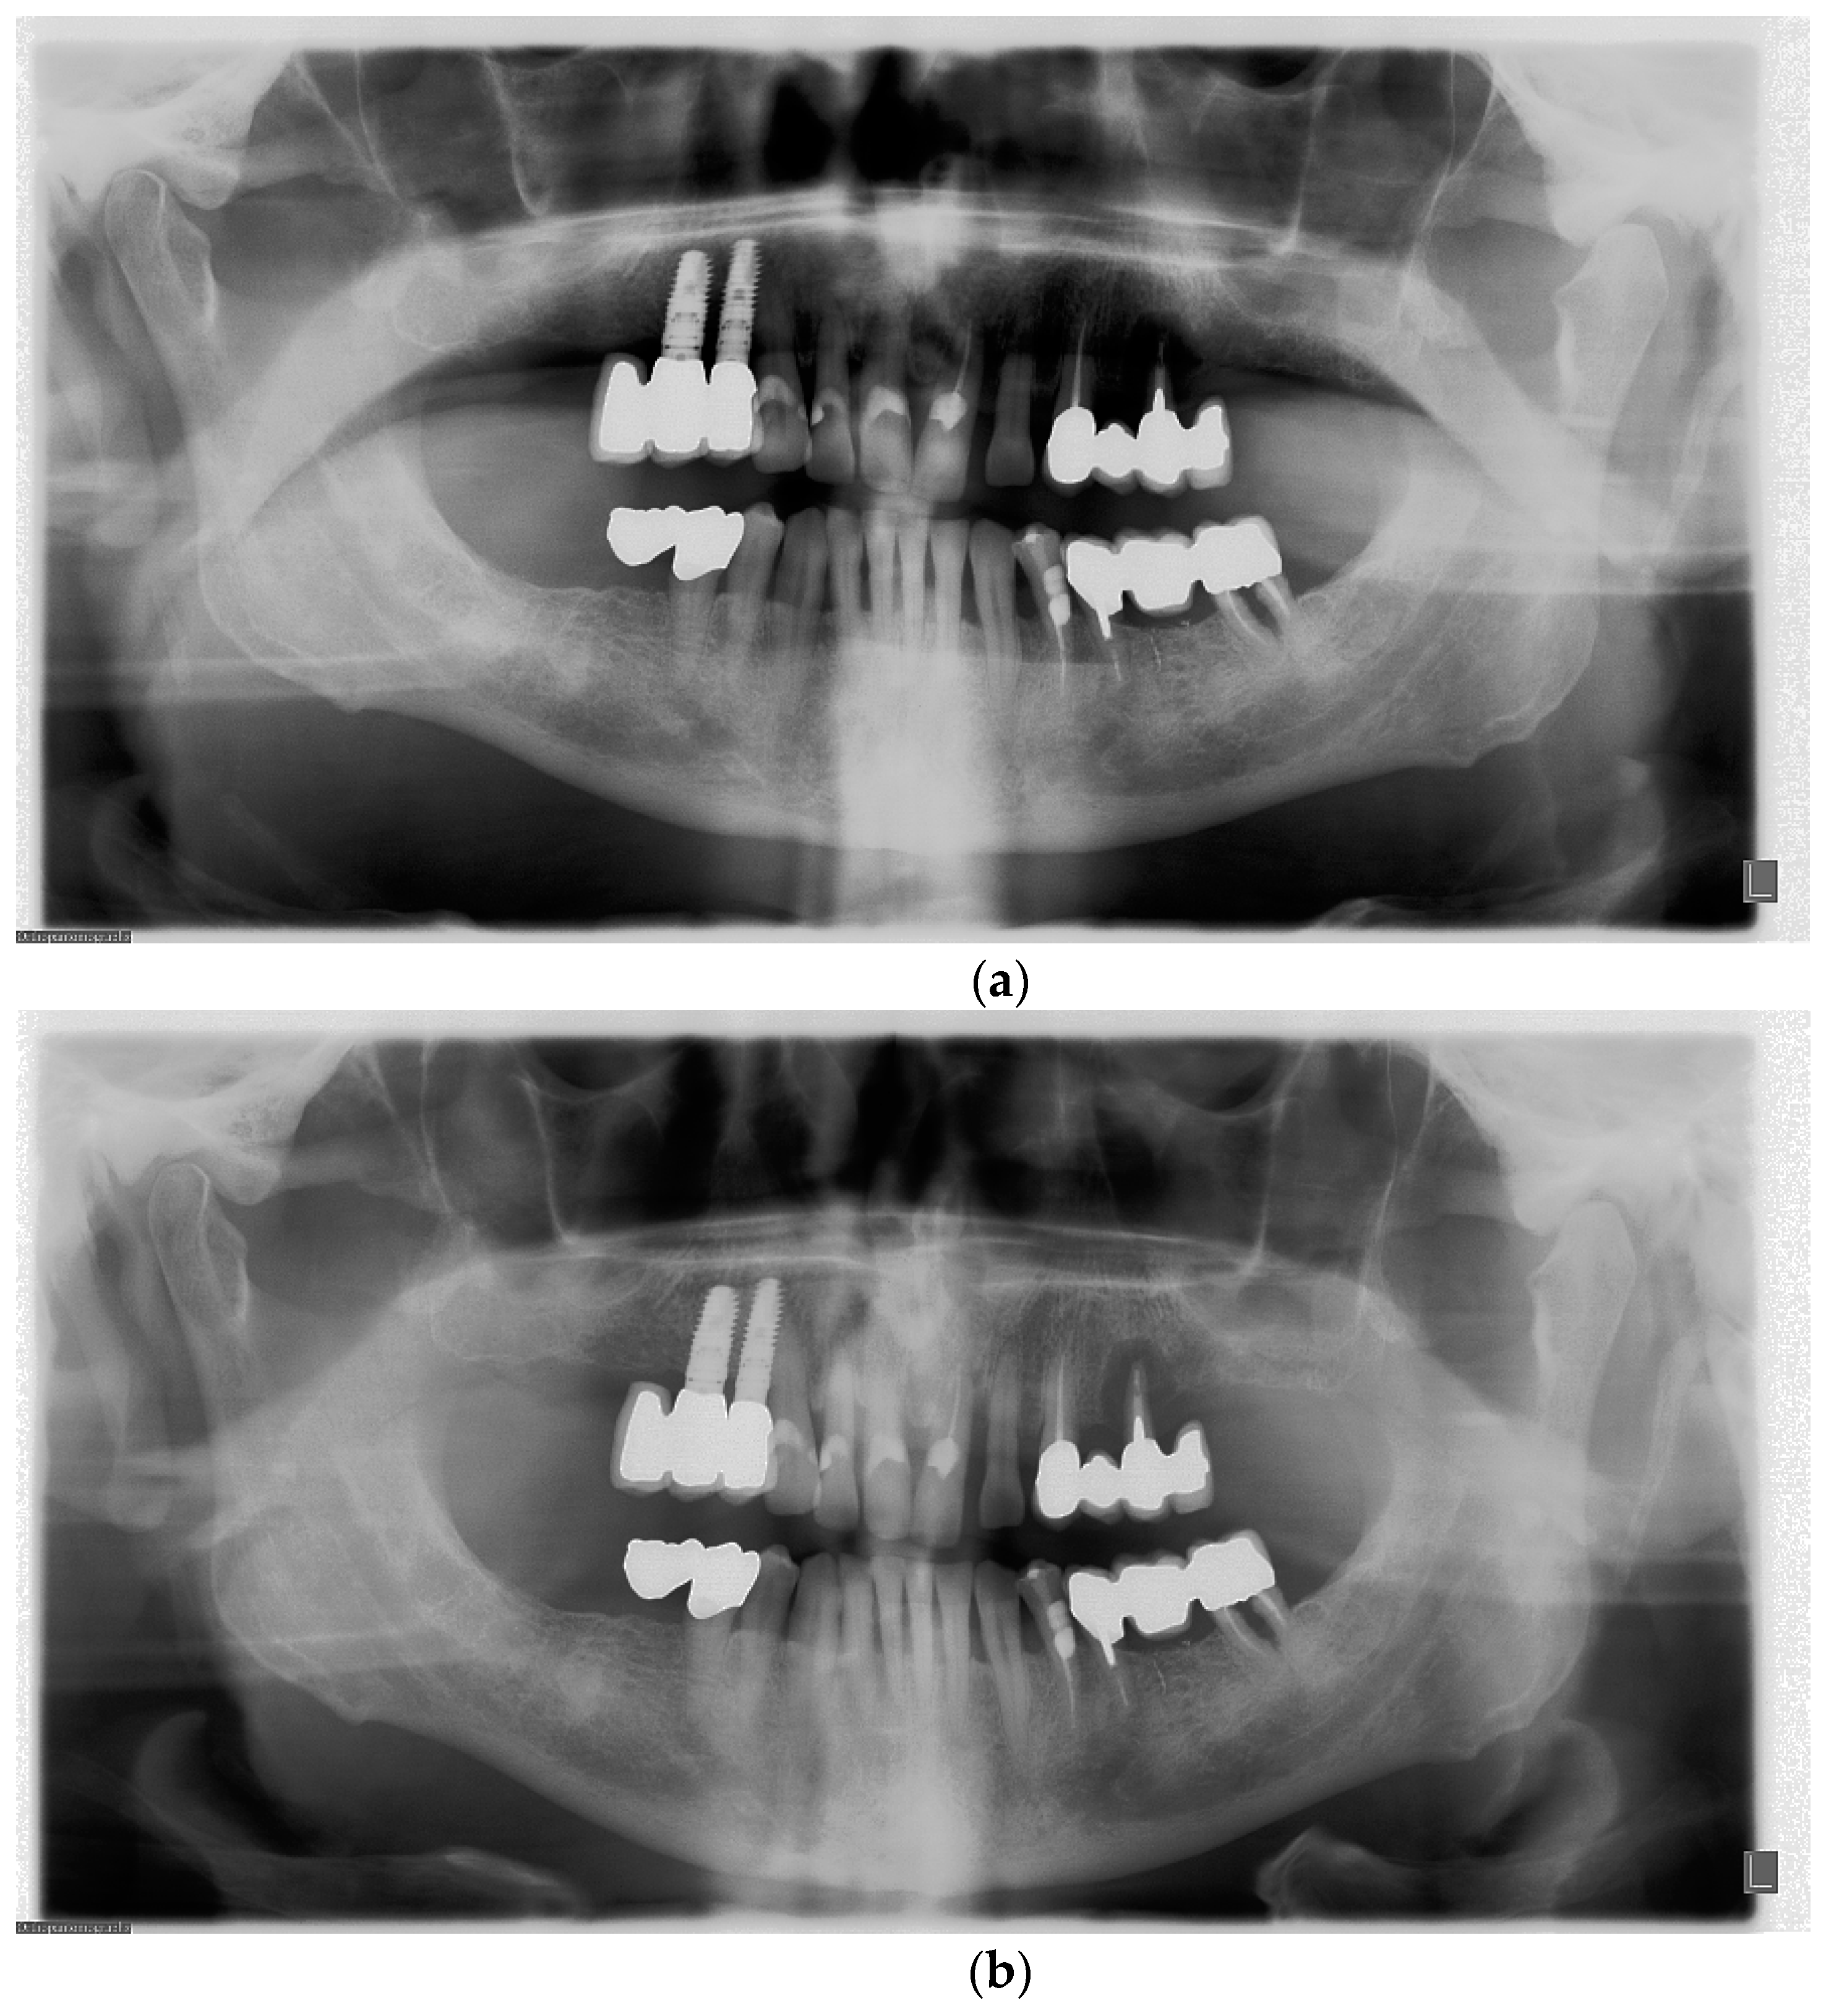

Dental Radiographic Errors And Artifacts . Correctly exposing intraoral receptors includes four basic steps: Errors and artefacts in dentomaxillofacial include positioning errors in intraoral techniques, panoramic radiography,. It identifies three main categories of errors: Radiographic film faults and artifacts in dentistry. As radiopaque artifact superimposed over the dental image. Also, excessive movement of the tube, the patient's head or the film may result in a variety of unusual radiographic flaws. The following is a list of some. Improper time selection is the most likely error because most. Incorrect exposure can be caused by many factors; March 2, 2017 by dr. The most common being improper exposure settings. Dental appliances left in the mouth during exposure, jewelry & eye. Receptor placement, vertical pid (cone) angulation alignment, horizontal pid (cone) angulation alignment, and central ray.

It identifies three main categories of errors: Errors and artefacts in dentomaxillofacial include positioning errors in intraoral techniques, panoramic radiography,. March 2, 2017 by dr. The most common being improper exposure settings. As radiopaque artifact superimposed over the dental image. Improper time selection is the most likely error because most. Incorrect exposure can be caused by many factors; Also, excessive movement of the tube, the patient's head or the film may result in a variety of unusual radiographic flaws. Radiographic film faults and artifacts in dentistry. Dental appliances left in the mouth during exposure, jewelry & eye.